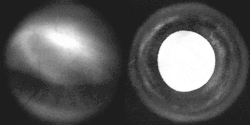

-

Iris, front view -

Fluorescein angiograpy of the iris reveals a radial layout of blood vessels.